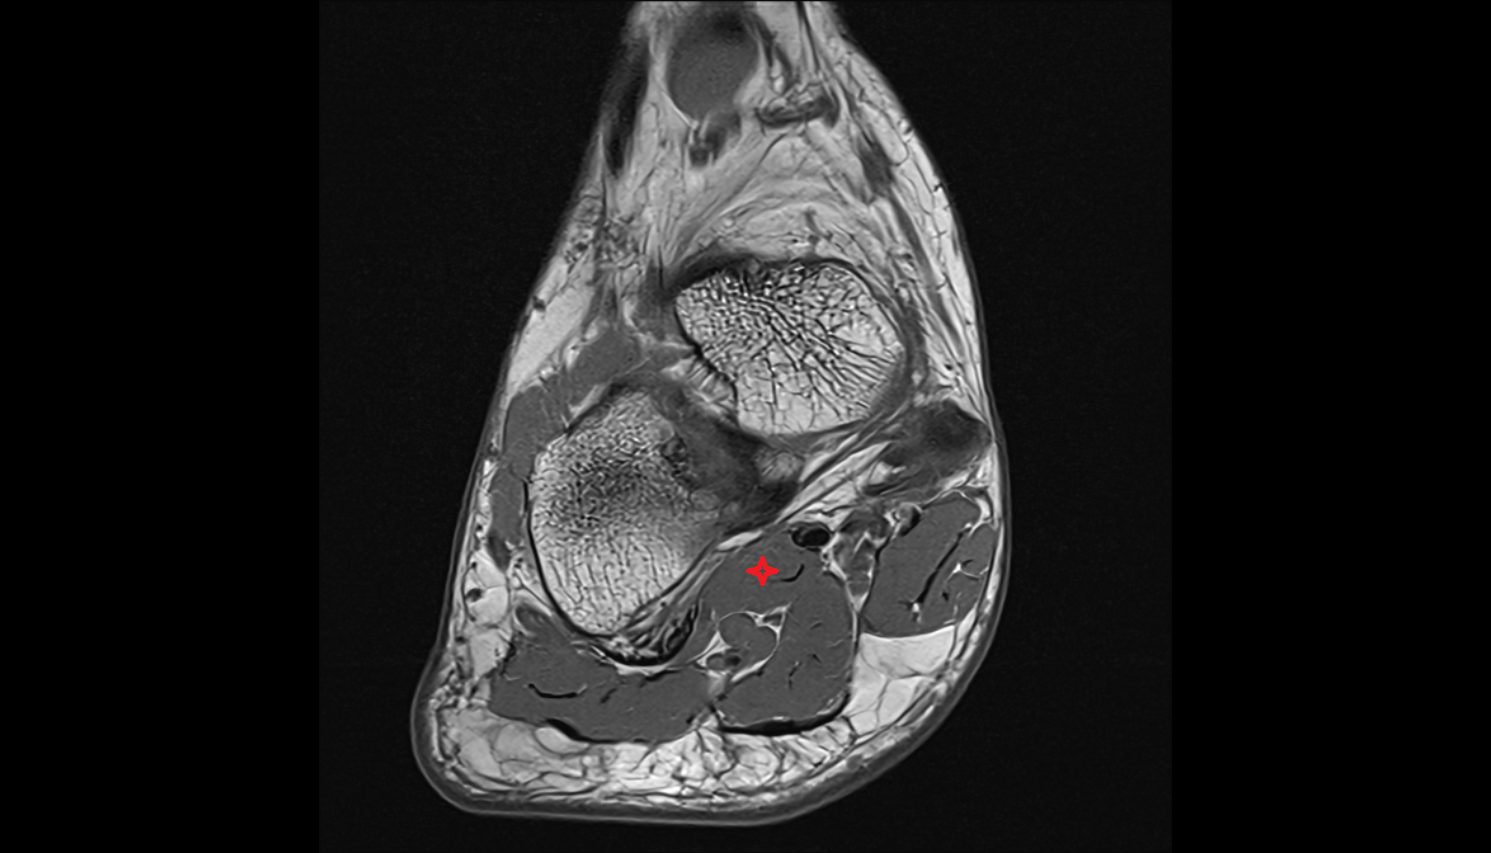

- Talus

- Head of talus

- Body of talus

- Neck of talus

- Calcaneus

- Sustentaculum tali

- Ankle joint

- Talocalcaneal joint

- Talocalcaneonavicular joint